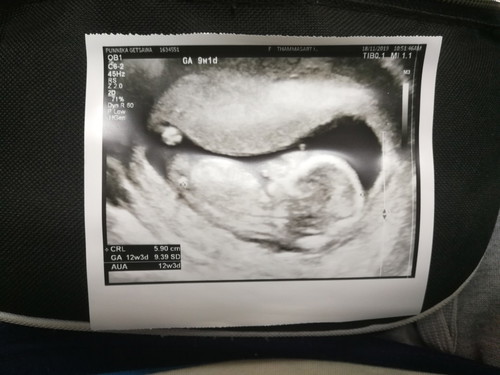

ขอคำแนะนำการดูแลลูกน้อยในครรภ์ ของแม่แต่ละบ้านด้วยค่ะ ตอนนี้เรา12W แล้ว